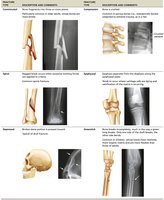

Fracture Classification

Position: Nondisplaced (normal alignment) vs. displaced (misaligned).

Completeness: Complete (all the way through) vs. incomplete.

Skin penetration: Open (compound) vs. closed (simple).